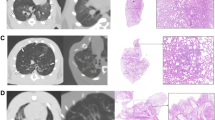

Extract: Lung lavage samples obtained from patients with cystic fibrosis (CF) had significantly higher levels of total protein per ml lavage fluid (0.49 vs. 0.30 mg/ml). A significant increase in the absolute and relative amounts of a low molecular weight glycoprotein (15,000 mol wt) was noted in lavage specimens from CF patients. Reserpine-treated rats also showed a significant increase in the total protein recovered in the lung lavage fluid with a 233% increase in the absolute and relative amounts of a low molecular weight glycoprotein (15,000 mol wt). Thus, reserpine induces changes in the secretions of the lung of the rat which are similar to those observed in samples obtained from the lungs of CF patients.

Speculation: The administration of reserpine to rats, which has been previously shown to produce morphologic changes in various exocrine tissues and abnormalities in the composition of submaxillary saliva similar to those reported for CF patients, should result in changes in the composition of other exocrine gland secretions.